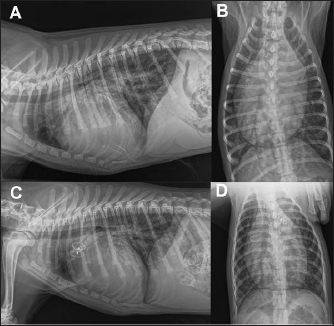

Thoracic radiographs showed left-sided cardiomegaly and pulmonary over circulation (Fig. 1). A transthoracic echocardiogram revealed severe left atrial and left ventricular dilation: left atrium/aorta (LA:Ao): 2.04, reference value: <1.6, normalized left ventricular internal diastolic diameter (LVIDDN): 3.02, reference value: ≤1.7) and large PDA, with an approximate minimal ostium and ampulla diameters of 5.2 and 10.3 mm (Fig. 2). Doppler echocardiography confirmed left-to-right flow across the PDA with a pressure gradient of 102 mmHg in systole and 41 mmHg in diastole. Mild mitral regurgitation was also noted.

Fig. 1. Thoracic radiographs, right lateral and dorso-ventral views, (A and B) before the surgery and (C and D) 24 hours later. Post-operative films show a reduction of the cardiac silhouette and of the pulmonary over-circulation, and correct device position.